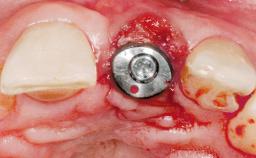

Immediate Placement of an Implant in a Maxillary Left Central Incisor Site

A 33-year-old female patient presented with an upper left central incisor that required extraction after a failed endodontic therapy. The tooth had been traumatized when the patient was a teenager and had undergone several endodontic treatments, including two apicectomy procedures. The patient was in good health and did not smoke. Clinical examination showed that the patient had a high lip line. In full smile, the gingival margins of the upper teeth were visible to the first molars. The gingival margins of central incisors 11 and 21 were only just showing. Examination of tooth 21 confirmed that the tooth was mobile and had hypererupted by 1 mm.

Type of Implants One-Piece

Placement Protocol Immediate implant placement

Tooth Site Maxillary incisor or canine

Socket Morphology Single-root socket

Socket Integrity Damage to one or more bone walls

Bone Volume Damage to one or more socket walls